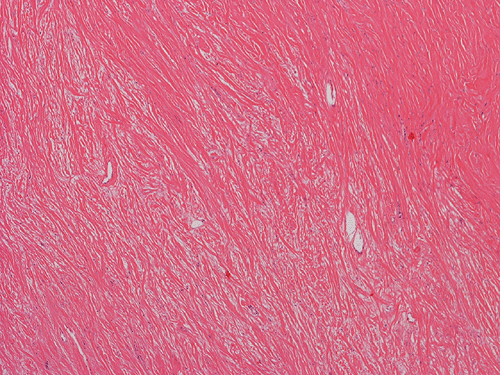

Pathology of the Case: Macroscopically, the nodules are well circumscribed, irregular, and stone hard. The cut surface is solid, gray-white, and free of necrosis. An intraoperative frozen section was performed to rule out metastatic carcinoma, Hodgkin's and non-Hodgkin's lymphoma, and sarcoma. Histologically, the material submitted for frozen section demonstrated hyalinized, hypocellular fibrous tissue with large, calcified nodules (Panel A and B). The section submitted for frozen sections was similar. The bulk of the specimen is composed of hypocellular, hyalinized collagenous tissue with occasional small irregular islands of chronic inflammatory cells (Panel C and D). The nuclei does not display significant nuclear atypia (Panel E). Many large psammoma bodies (Panel F and G)  are present and they are not associated with inflammatory cells. There are also extensive areas with no evidence of either calcifying nodules or inflammatory cells (Panel H). A segment of colon was also resected and the pathology is consistent with Crohn's disease.

Calcifying fibrous tumors are often well circumscribed, firm masses most commonly ranging in size from 1 to 4 cm in greatest dimension. However, the lesions can reach up to 15 cm.  Microscopically, the tumor is a well circumscribed mass showing diffuse hyalinization and benign appearing spindle cells intermixed with a prominent chronic inflammatory infiltrate. The inflammatory component is composed mainly of lymphocytes, eosinophils, and mast cells.  There is usually no hypercellular areas, significant atypia, or mitotic activity. Necrosis and hemorrhage are not seen. This lesion is not infiltrative. As the name implies, a hallmark of the lesion is the presence of calcifications, which may be psammomatous or dystrophic and are sometimes associated with foreign body type giant cell reaction.  It is believed these lesions are reactive because there is no documented evidence of cytogenetic or molecular disruptions that may suggest clonality 8